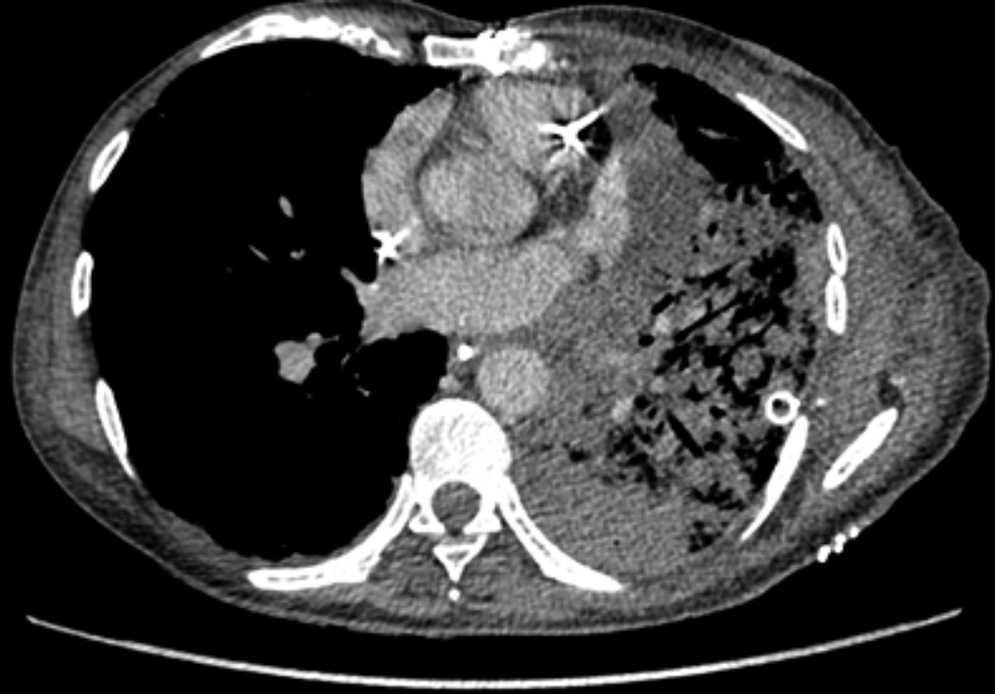

Pulmonary vein obstruction is usually an early complication, occurring during the first few hours after transplantation, and causes severe symptoms. Marked hypoxia, pulmonary edema, and pulmonary infiltrates are observed. If the lower lobe is more severely affected, a high suspicion for such a complication is warranted, and an early additional diagnostic test should be ordered. The initial test should be a transthoracic or transesophageal echocardiogram, in spite of this test being only useful for diagnosis when performed by an experienced operator, due to a challenging visualization and interpretation after recent surgery 6. Alternatively, chest CT angiography can be used, which also allows artery suture and distal vascularization to be assessed and reconstructions to be produced. CT angiography establishes the diagnosis in most cases. Anticoagulation using heparin and clinical course monitoring is used to manage partial thromboses and stenoses. In the event of a complete vein obstruction or a poor course, in patients with a very recent surgery, re-transplantation or lobectomy for double-lung transplantations, may be needed. If the patient is in a stable condition, several days have elapsed, and anatomic characteristics are favorable, an angioplasty with dilation and stent implant can be considered.

Figure 3. Coronal view in CT angiography showing complete lower pulmonary vein obstruction after left lung transplantation.

Figure 4. CT image showing extensive lung infiltrates in lower left lobe resulting from lower pulmonary vein obstruction.